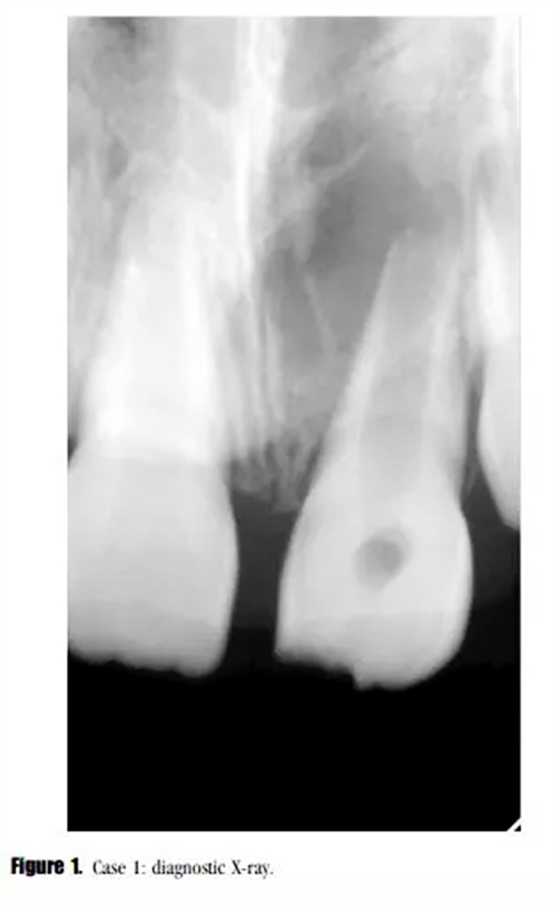

主訴:左上恒中切牙腫脹。(圖1)

影像學檢查: X線顯示,21根尖發(fā)育達到第三階段,根尖區(qū)被大面積低密度透射影像包繞?;佳辣辉\斷為慢性根尖周炎急性發(fā)作。

在3,6,9個月的隨后跟蹤隨訪中,患者完全沒有癥狀。與鄰牙和對側(cè)牙對比,21的叩診、捫診以及牙周袋深度都在正常范圍內(nèi)。對于牙髓溫度測試沒有反應(yīng)。影像學評估顯示,根尖區(qū)低密度透射影像范圍減小,牙根發(fā)育為I型(按照Chueh等人的研究)(圖2),